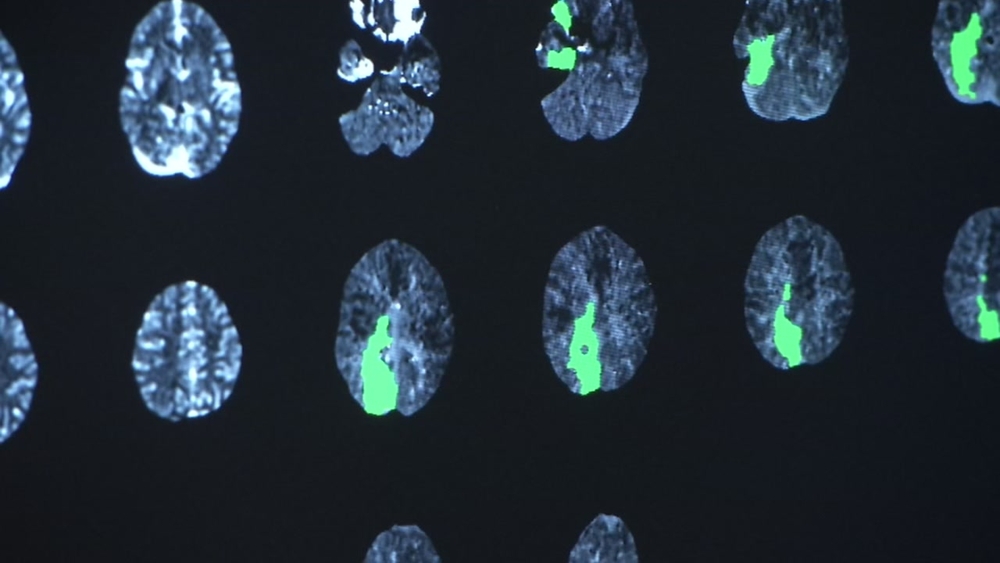

"A cluster of blood cells that burst in my brain and it caused a hemorrhagic stroke," she said.

The massive stroke crippled her. But perhaps worst of all, it paralyzed part of her face. "I looked in the mirror and I saw my face for the first time and I was shocked. I felt that my identity was completely gone, you know," Hernandez said.